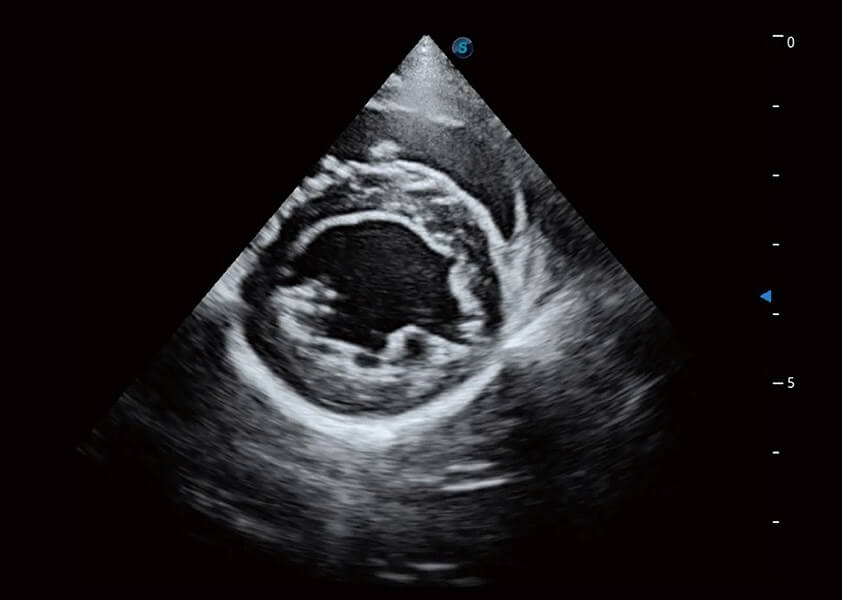

心脏解决方案

ProPet 60 配备了丰富的心脏探头群、先进的成像技术和专业的心脏测量工具,可帮助动物医生为不同体型和生理结构的动物提供心脏和心肌功能的全面评估。

• TDI 组织多普勒成像

实时用颜色表示心肌组织运动,观察和定量组织的运动情况,对快速检测与评估心肌的灌注和活性、电传导及心肌收缩和舒张功能等均能提供重要的诊断信息。

• MQA 心肌定量分析

通过心肌识别技术与二维斑点追踪技术相结合,对心脏的超声图像进行量化分析。计算心肌17个节段的应变、应变率、速度、位移等,并通过牛眼图的形式进行呈现。

• AMM 解剖M型

通过360度任意调节3条M型取样线,在同一心动周期上观察心脏不同位置的运动曲线,得到准确的心功能测量数据,有效评估心肌运动及左心室功能。

(犬)乳头肌短轴